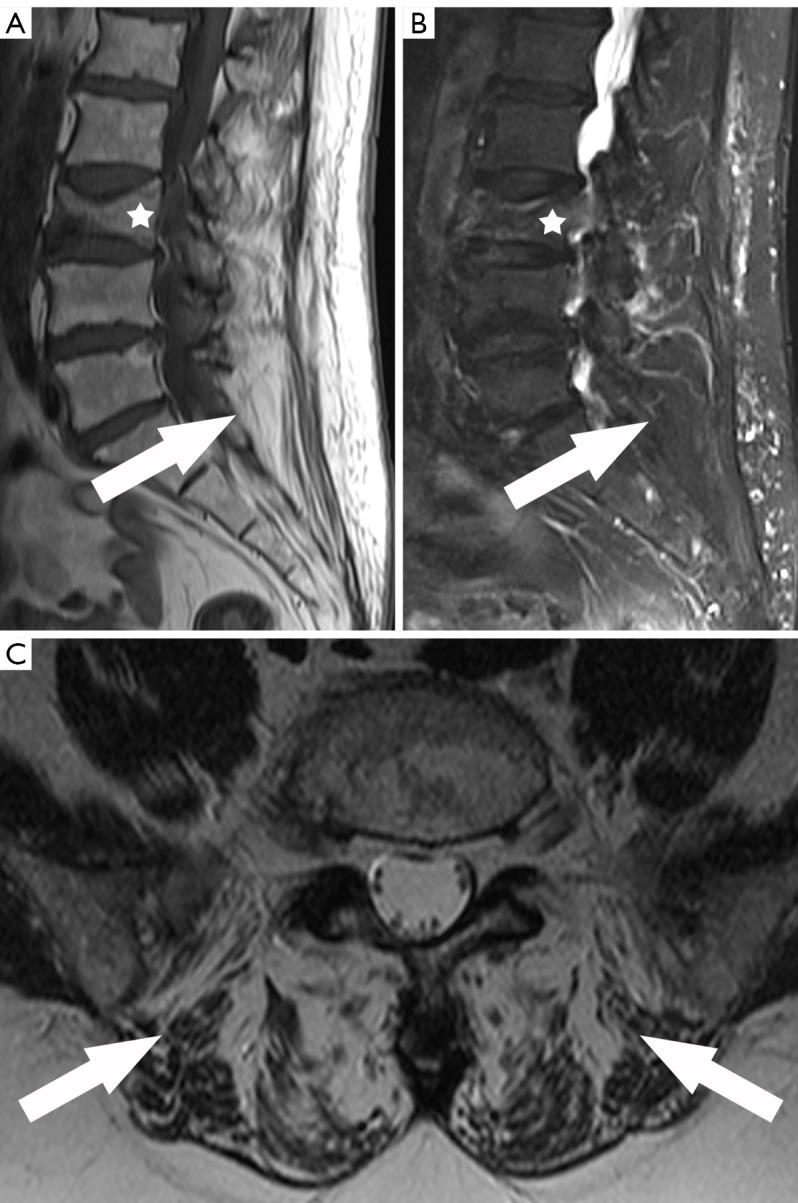

Computed tomography (CT) and magnetic resonance imaging (MRI) of the spine are fundamental non-invasive tools to investigate the status of the bone and soft tissue in vivo. A novel and promising approach is to investigate the quality and quantity of paraspinal muscles even beyond the clinical question. The aim of the present review is to summarize current evidence on CT and MRI about the relationship between paraspinal muscular status and bone health in osteoporosis (OP) and fracture risk.

Research investigating the intricate interplay between musculature and bone health reveals that degenerating paraspinal muscles, characterized by shrinking and fatty infiltration, are associated with lower bone mineral density (BMD) and the development of OP. Additionally, research indicates that weaker paraspinal muscles are linked to a higher risk of fractures, including those at the spine.

脊柱计算机断层扫描(CT)和磁共振成像(MRI)是研究体内骨骼和软组织状况的基本无创工具。一种新颖且有前景的方法是,甚至超出临床问题范畴来研究椎旁肌肉的质量和数量。本综述的目的是总结当前关于CT和MRI的证据,以探讨骨质疏松症(OP)中椎旁肌肉状态与骨骼健康之间的关系以及骨折风险。

对肌肉组织与骨骼健康之间复杂相互作用的研究表明,以萎缩和脂肪浸润为特征的退化性椎旁肌肉与较低的骨矿物质密度(BMD)以及OP的发生有关。此外,研究表明较弱的椎旁肌肉与更高的骨折风险相关,包括脊柱骨折。